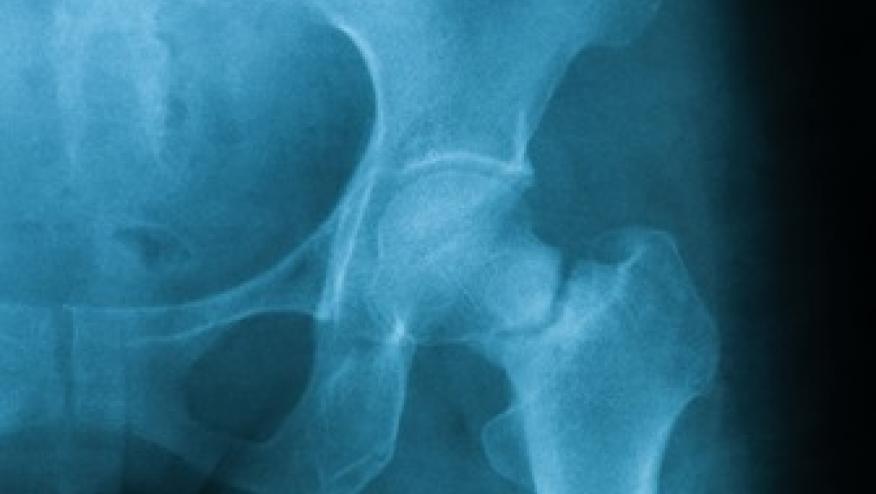

A randomized 24-month trial enrolled 4093 postmenopausal women with osteoporosis and a fragility fracture and treated them with either monthly subcutaneous romosozumab (210 mg) or weekly oral alendronate (70 mg) for 12 months, followed by open-label alendronate. The primary endpoints were cumulative fracture incidence at 2 years.

Hip fracture was lower by 38% in the romosozumab-to-alendronate group.